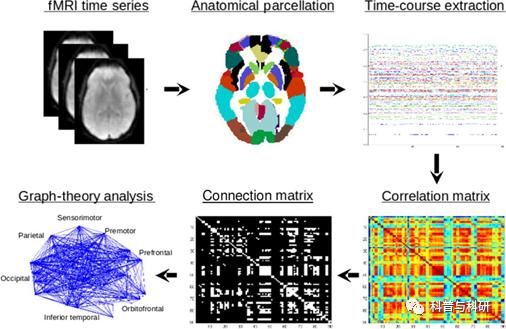

CONN工具箱介绍 |

1、Conn数据预处理批处理过程讲解 2、静息态功能连接分析 |

网络及局部指标实操 |

1、静息态独立成分分析(ICA) 2、局部相关,全脑相关,径向相关,径向相似性等指标计算 3、大尺度脑网络功能连接计算 4、CONN工具箱各指标的统计分析 5、各个指标的结果呈现 6、CONN工具箱各个指标手把手实操练习 |

CONN工具箱介绍、各个网络及局部指标实操 |

1、静息态功能连接分析 2、动态功能连接分析(简单演示) 3、静息态独立成分分析(ICA) 4、局部相关,全脑相关,径向相关,径向相似性等指标计算 5、ALFF/fALFF等指标计算 6、图论分析 |

CONN工具箱与功能连接分析 |

1、CONN工具箱各指标的统计分析 2、各个指标的结果呈现 3、CONN工具箱各个指标手把手实操练习 |

基于多模态磁共振影像的人脑连接组学介绍 |

基于静息态 fMRI 的 脑功能网络构建 |

1、基于GRETNA 静态功能网络构建 2、脑网络拓扑属性介绍 3、脑网络拓扑属性计算 |